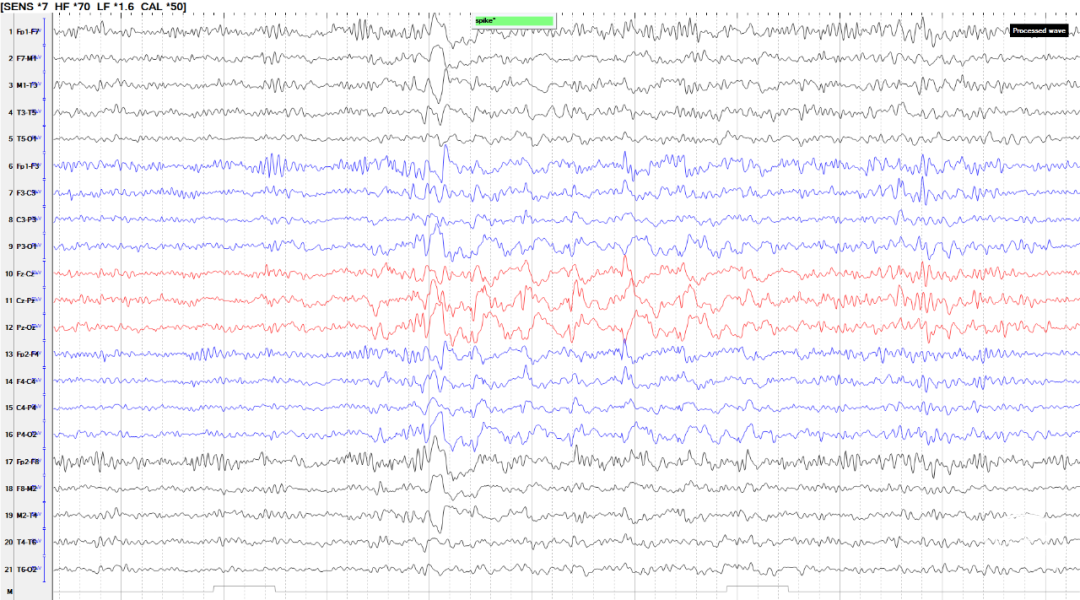

患者于5月龄首发,诱因:发热1周,热峰40℃,表现为发热第1天出现双眼上翻,无肢体抽搐,持续数分钟;15月龄学步后发现行走易跌倒,坐位时出现头颈及躯干向一侧倾斜,每次持续2-3秒,每天发作数次,声音刺激可诱发;病程中仅17岁出现1次全身僵直抖动;23岁后发作较前稍有缓解,声音刺激无发作,平均1-3次/天,表现为:发作性肢体僵直,每次持续2-3秒;患者幼年起病,辗转多家医院仍发作频繁,反复跌倒至头面部频繁外伤。后转求我院,完善脑电图检查提示清醒期背景活动正常(图1),间歇期放电,弥漫性,中线-右旁中线著(图2-3),2天共监测到30次临床发作,表现为强直发作,累及颈肌、躯干、四肢,以左侧肢体为著;同步脑电图示弥漫性低波幅快节律,以中线-右侧旁中线为著(图4-5)。头颅MRI可见双侧岛叶、基底节、枕叶异常信号(图6)。头颅PET见提示多发低代谢区(图7)。

图2-3.间歇期放电弥漫性,中线-右旁中线著